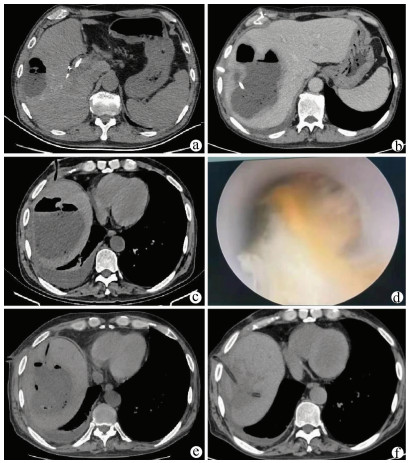

A case of huge intrahepatic biliary papillomatosis

Ziyue WANG, Daqun LIU, Jiaao YU, Jingxuan ZHANG, Guoyue LYU

2021, 37(11): 2651-2652. DOI: 10.3969/j.issn.1001-5256.2021.11.034

Abstract(849) HTML (182) PDF (2663KB)(60)

Abstract: